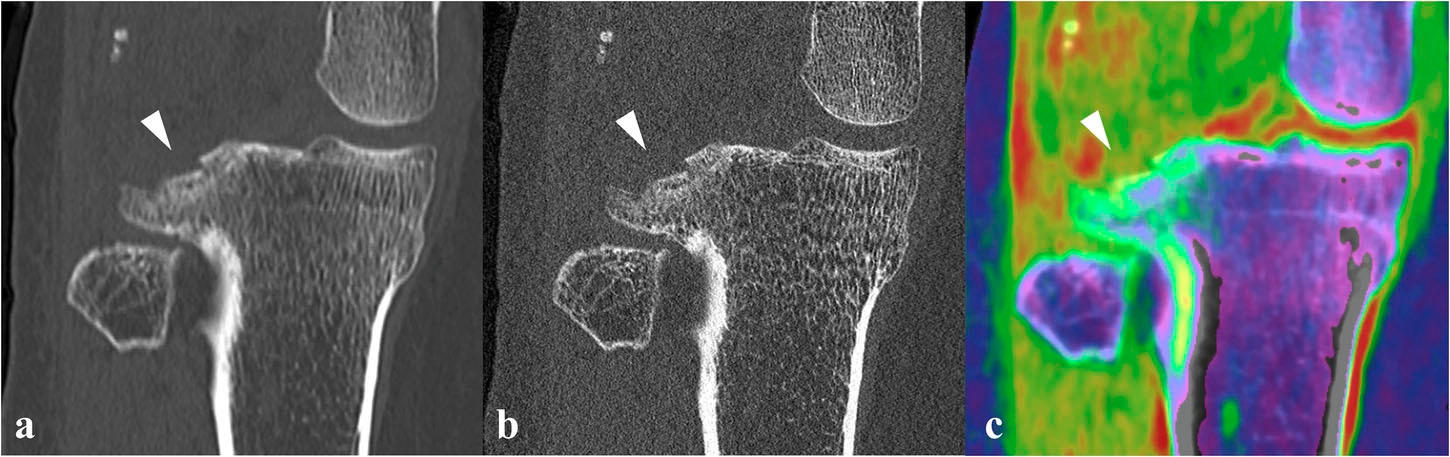

Le scanner à comptage photonique pourrait être une alternative efficace à l’IRM pour l’évaluation des blessures du genou, selon une étude présentée dans European Radiology Experimental [1]. Ses auteurs, chercheurs à l’université de Maastricht, aux Pays-Bas, ont étudié sur fantôme et chez une première patiente, les possibilités de cette nouvelle technologie, qui offre à la fois une résolution supérieure au scanner classique et la possibilité de différencier les tissus grâce à l’imagerie spectrale. « L’IRM est reconnue comme une modalité de référence pour une caractérisation précise des blessures du genou, mais elle n’est pas toujours disponible et peut être contre-indiquée chez certains patients, ce qui rend urgent le besoin de trouver des alternatives », justifient-ils.

Pour visualiser la moelle osseuse et les blessures des tissus mous, ils ont adapté une technique basée sur l’image développée pour le scanner double énergie classique. Un algorithme permet de retire